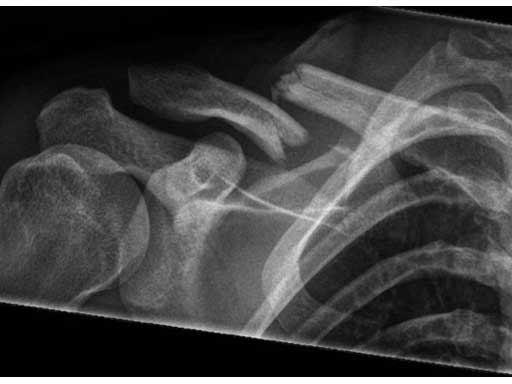

A 21-year old male fell on the right shoulder when playing soccer. He sustained a cavicular shaft fracture type 06 A3 (OTA classification) with dislocation of shaft width and shortening of around 2 cm.

Fig 1ab Preoperative x-rays.